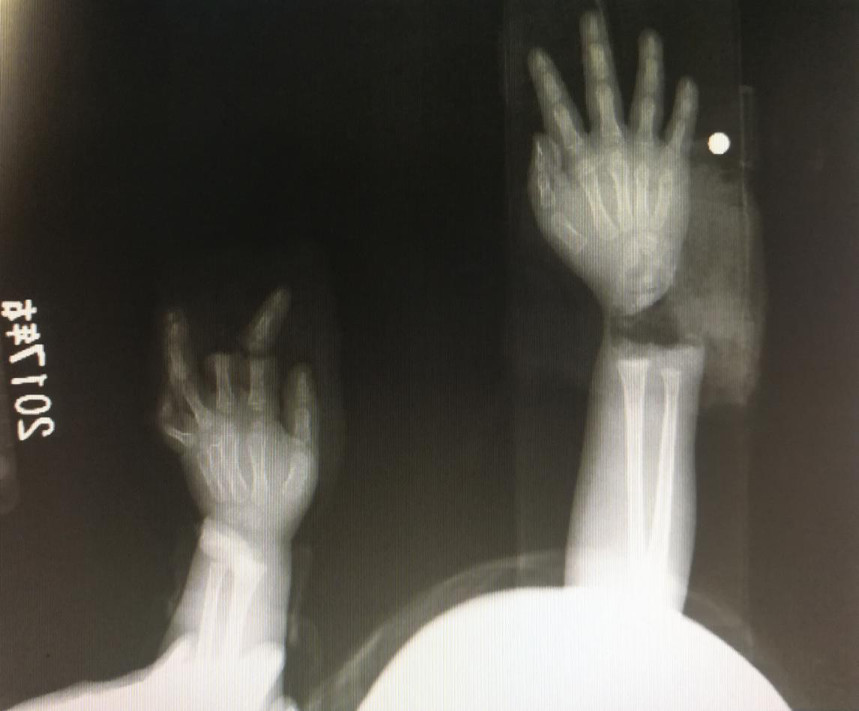

“急診在哪,急診在哪”,伴隨著一聲聲急促的問詢,一位年輕女士抱著渾身是血的小孩疾步前往急診室,懷里的小孩在疲憊與疼痛的交織下,時睡時醒。鑒于小孩的情況,急診醫(yī)生迅速安排給小孩拍了X光片,影像片結果顯示小孩左手手腕完全離斷,右手中、食指離斷,距離事發(fā)時間已經(jīng)3個多小時,需盡快安排手術。

經(jīng)過長達5個多小時的手術,小宇(化名)終于被送出了手術室,離斷的手腕和手指均已完成再植,但關于斷指的存活與否還需要經(jīng)過一個十天的觀察期。小宇的主治醫(yī)生是長沙年輪骨科醫(yī)院手足外科馬思成醫(yī)生,據(jù)馬醫(yī)生介紹,小宇受傷情況比較嚴重,失血過多,而且兩個手都存在完全離斷的情況,手術時安排了兩組醫(yī)生同時進行,整個手術過程比較順利,目前小宇還處于觀察期。